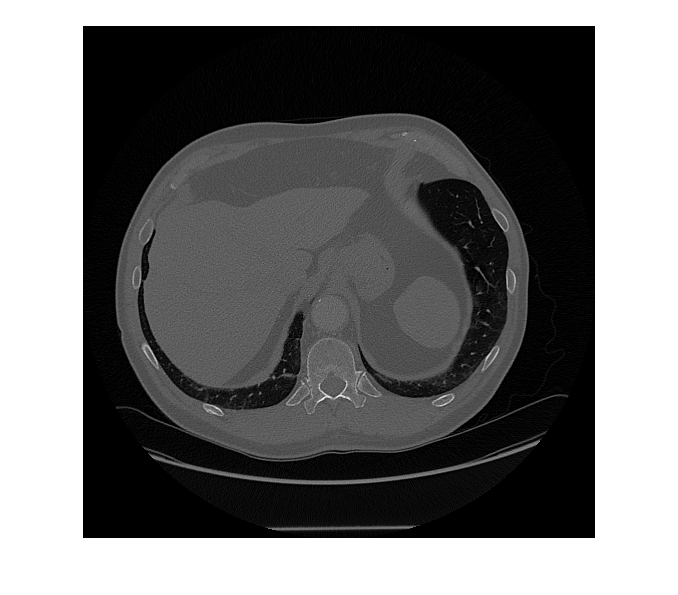

Segment objects in medical image using Medical Segment Anything Model (MedSAM) image embeddings

[

segments objects from an image of size mask,score] = segmentObjectsFromEmbeddings(medsam,embeddings,imageSize,BoundingBox=boxPrompt)imageSize using the Medical

Segment Anything Model (MedSAM) image embeddings embeddings and the

bounding box coordinates boxPrompt as a visual prompt, and returns the

predicted object mask mask and the corresponding prediction score

score.